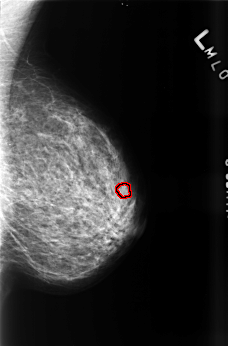

FILE: B_3460_1.LEFT_MLO.OVERLAY

TOTAL_ABNORMALITIES 1

ABNORMALITY 1

LESION_TYPE CALCIFICATION TYPE PLEOMORPHIC DISTRIBUTION CLUSTERED

ASSESSMENT 4

SUBTLETY 3

PATHOLOGY BENIGN

TOTAL_OUTLINES 1

BOUNDARY